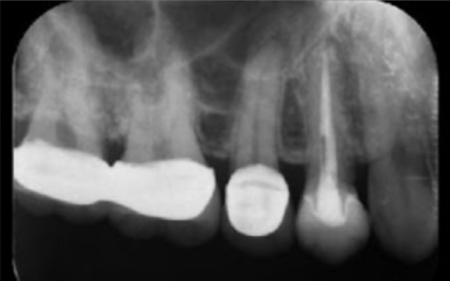

40代女性 炎症を起こした右上奥歯にマイクロスコープを用いた精密根管治療を行った症例

拝見したところ、右上奥歯(第2小臼歯)には保険診療の白い被せ物であるCADCAMが装着されていました。

レントゲン撮影をして検査すると、その手前の右上奥歯(第1小臼歯)には神経や血管が通る根管に清掃と消毒を行う根管治療が施されていました。しかし、歯の内部に細菌が侵入して炎症を起こし、歯根の先に膿が溜まる根尖病巣(こんせんびょうそう)を発症している状態です。

レントゲン撮影で根尖病巣の治癒を確認後、最終的な被せ物を作製するため、歯の形を整えてから型取りを行います。

後日、完成したセラミッククラウンを装着し、噛み合わせや見た目に問題がないかを確認して、治療を終了しました。